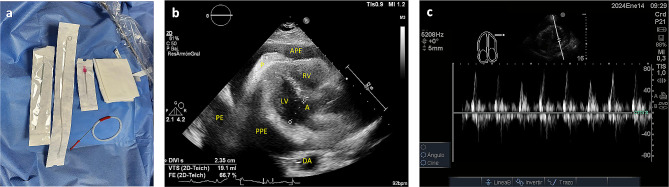

心包穿刺术很常见,通常通过剑突下入路进行,但也有其他经胸入路的描述。这篇简短的文章介绍了一种使用线性换能器并在超声波实时引导下,通过前方途径进行的非平面技术超声引导心包穿刺术,该方法具有持续追踪针头的优势,可减少与该方法相关的并发症,如气胸、心脏穿刺不慎和左乳内动脉(LIMA)损伤等。

The pericardiocentesis procedure is common, often performed via the subxiphoid approach, although other transthoracic approaches have been described. This short communication describes an off-plane technique ultrasound-guided pericardiocentesis using an anterior approach, performed using a linear transducer and guided in real-time by ultrasound, offering the advantage of continuous needle tracking to reduce complications associated with this approach such as pneumothorax, inadvertent cardiac puncture, and injury to the left internal mammary artery (LIMA).